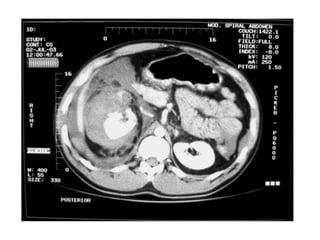

CT Scan

•Gold Standard

•Haemodynamically Stable

• Provides excellent imaging of

pancreas, duodenum and Genitourinary system

•Standard for detection of solid organs injury.

• Determines the source and amount of bleeding

• Can reveal other associated injuries e.g.

Vertebral & Pelvic # & injury in the thoracic

cavity .

•High Specificity-95%